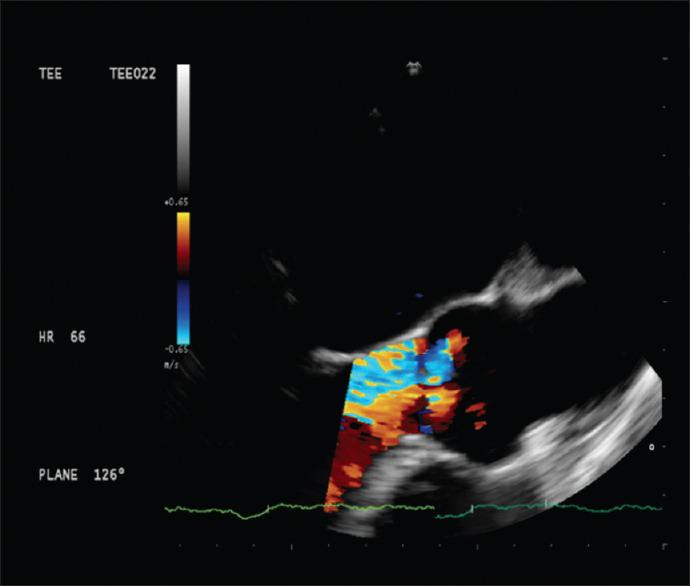

经食管超声心动图在原位肝移植中的应用:一篇叙述性综述。

Utility of transesophageal echocardiography during orthotopic liver transplantation: A narrative review.

Orthotopic liver transplantation (OLT) is the standard of care for patients suffering from end stage liver disease (ESLD). This is a high-risk procedure with the potential for hemorrhage, large shifts in preload and afterload, and release of vasoactive mediators that can have profound effects on hemodynamic equilibrium. In addition, patients with ESLD can have preexisting coronary artery disease, cirrhotic cardiomyopathy, porto-pulomary hypertension and imbalanced coagulation. As cardiovascular involvement is invariable and patient are at an appreciable risk of intraoperative cardiac arrest, Trans esophageal echocardiography (TEE) is increasingly becoming a routinely utilized monitor during OLT in patients without contraindications to its use. A comprehensive TEE assessment performed by trained operators provides a wealth of information on baseline cardiac function, while a focused study specific for the ESLD patients can help in prompt diagnosis and treatment of critical events. Future studies utilizing TEE will eventually optimize examination safety, quality, permit patient risk stratification, provide intraoperative guidance, and allow for evaluation of graft vasculature.

原位肝移植(OLT)是治疗终末期肝病(ESLD)患者的标准方法。这是一种高风险的手术,可能会导致出血、前负荷和后负荷的大幅变化,以及血管活性介质的释放,这些都会对血液动力学平衡产生深远影响。此外,ESLD 患者可能存在先前存在的冠状动脉疾病、肝硬化性心肌病、门肺高压和凝血失衡。由于心血管受累是不可避免的,并且患者在术中心脏骤停的风险相当大,因此在没有使用 TEE 禁忌的情况下,TEE 越来越成为 OLT 期间常规使用的监测手段。由经过培训的操作人员进行的全面 TEE 评估提供了大量关于基线心脏功能的信息,而针对 ESLD 患者的重点研究有助于快速诊断和治疗危急事件。未来使用 TEE 的研究最终将优化检查的安全性、质量,允许患者进行风险分层,提供术中指导,并评估移植物血管。